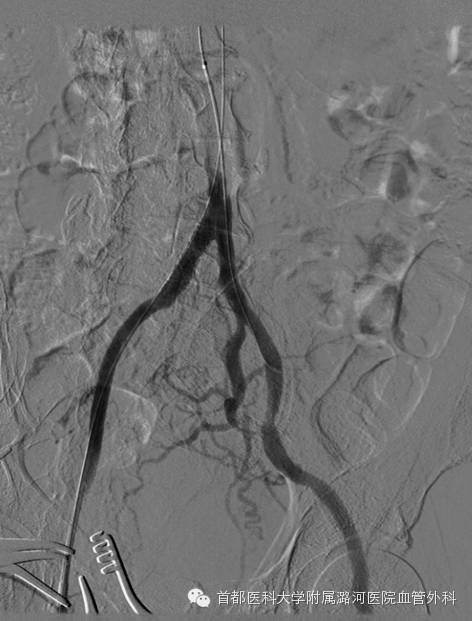

杂交手术室右侧股动脉切开透视直视下双腔取栓导管取栓;取栓成功;长段闭塞,TASC  D级病变转变为TASC  A级病变

球囊扩张支架支架置入术,放置一枚支架即可。